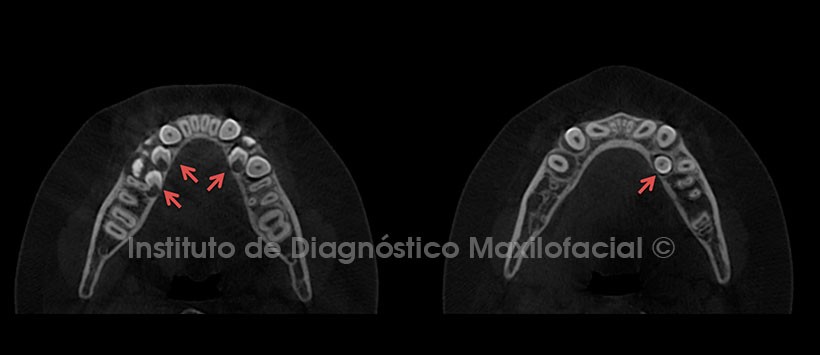

A la evaluación de la tomografía volumétrica (CBCT) en cortes axiales (Figura 2), coronales (Figura 3) y sagitales (Figura 4), se observan los folículos antes descritos en evolución intraósea, con proximidad hacia la tabla ósea lingual, sin causar alteración de las estructuras adyacentes.